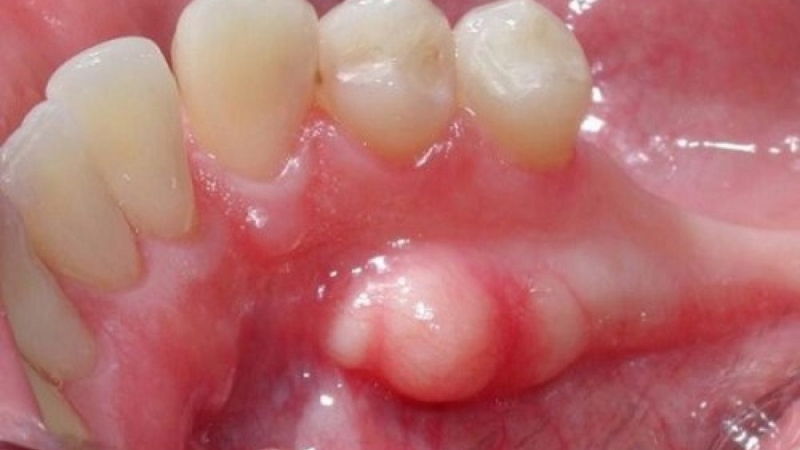

Bệnh lý lồi xương hàm dưới có tên tiếng Anh là Torus, đây là hiện tượng xương đặc bị lồi và khối xương khi lồi ra phổ biến nhất có dạng hình tròn, bề mặt nhẵn và xuất hiện ở hàm dưới. Khi phần xương này lồi ở hàm trên được gọi là lồi xương hàm trên.

Tình trạng bệnh lồi xương hàm dưới không phải là khối u tự pháp, chúng có tốc độ phát triển khá chậm và lành tính với bệnh nhân. Lồi xương hàm dưới thường gặp nhất ở 2 vị trí là sau vùng răng nanh hoặc răng cối nhỏ. Khi có phần xương lồi ra phát triển ở đường giữa và trong vòm miệng.

Tình trạng lồi xương hàm dưới rất khó phát hiện ở giai đoạn đầu, khi phần xương lồi ra ít và còn nằm dưới nướu. Theo thời gian, khối xương này phát triển to hơn, lồi hẳn ra ngoài là thời điểm đa số bệnh nhân phát hiện bệnh và không khỏi lo lắng. Tuy nhiên, lồi xương hàm dưới là u lành tính và phát triển rất chậm đến một kích thước nhất định nên bạn không nên quá lo lắng, hãy theo dõi sức khỏe và đến bệnh viện thăm khám khi cần.